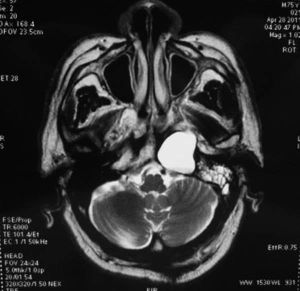

化膿性中耳乳突炎出現格氏征,或在簡單乳突鑿開後突然流膿增多,球後劇痛和復視,即可確診。乳突X線攝片及CT岩骨掃描,可見岩骨有骨質破壞。